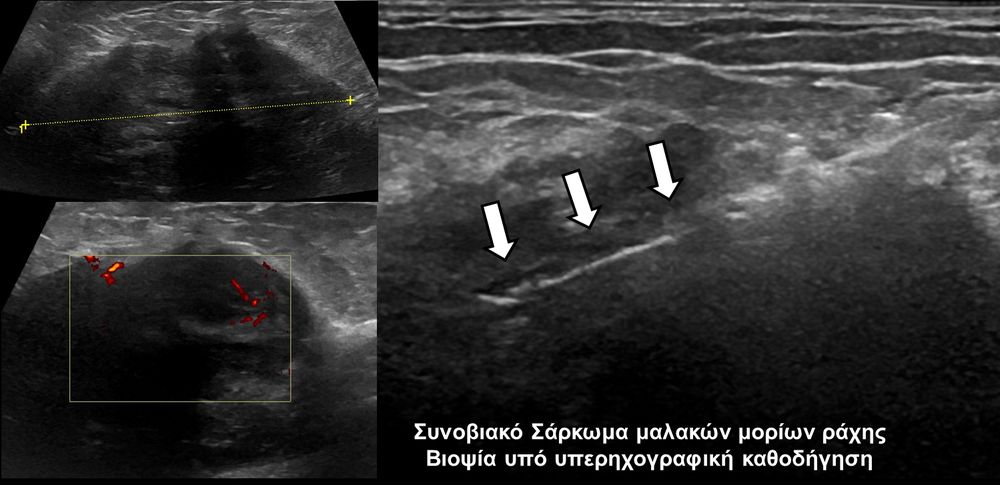

Η οστική βιοψία και η βιοψία όγκων μαλακών μορίων χρησιμοποιείται για την ιστολογική διάγνωση αλλοιώσεων (καλοήθων - κακοήθων / πρωτοπαθών ή μεταστατικών) ή για τη λήψη υλικού προς καλλιέργεια ώστε να αναδειχθεί το μικρόβιο που προκαλεί τη λοίμωξη του μυοσκελετικού συστηματος (πχ σπονδυλοδισκίτιδα). Η βιοψία υπό συνεχή απεικονιστική καθοδήγηση συμβάλλει στην υψηλή ακρίβεια τοποθέτησης της βελόνης εντός της βλάβης με ασφαλή προσπέλαση. Η χρήση σύγχρονων ομοαξονικών συστημάτων βιοψίας (coaxialtechnique) επιτρέπει την λήψη πολλαπλών δειγμάτων με μια μόνο παρακέντηση.